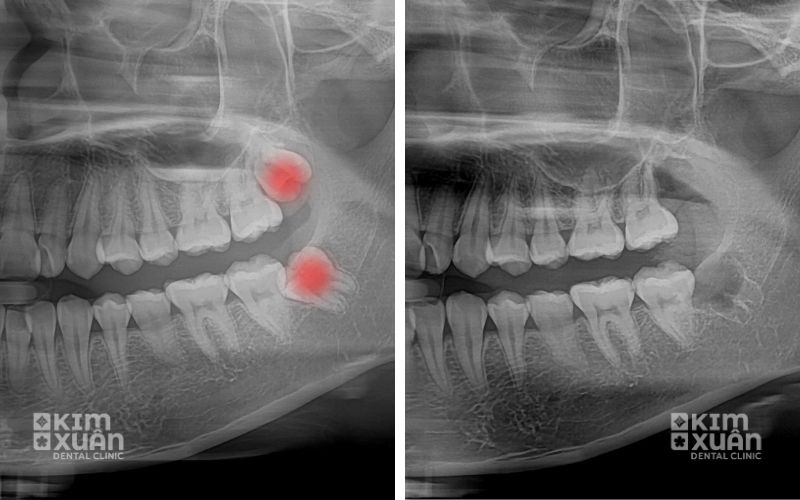

2.1. Răng khôn mọc lệch, mọc ngầm

Đây là tình trạng phổ biến nhất. Răng khôn có thể mọc nghiêng về phía răng số 7, mọc kẹt dưới nướu hoặc nằm sâu trong xương hàm. Tình trạng này dễ gây:

Nếu không nhổ sớm, răng khôn mọc lệch có thể gây viêm nhiễm lan rộng và làm xô lệch toàn hàm răng.